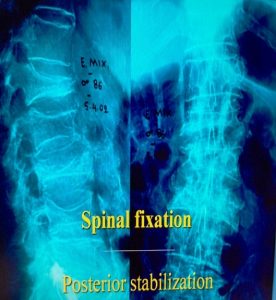

Σε ειδικές περιπτώσεις απαιτείται να γίνει και εσωτερική σταθεροποίηση της περιοχής του κατάγματος με σύστημα κοχλιών και ράβδων (εικόνα 4 α,β)

Εικόνα 4 α,β : προεγχειρητική πλαγία και προσθιοπισθία ακτινογραφία της Θ.-ΟΜ.Σ.Σ του Ε.Μ. 86 χρονών. Παρατηρείται η ύπαρξη πολλών σπονδυλικών καταγμάτων συνεπεία οτεοπόρωσης.